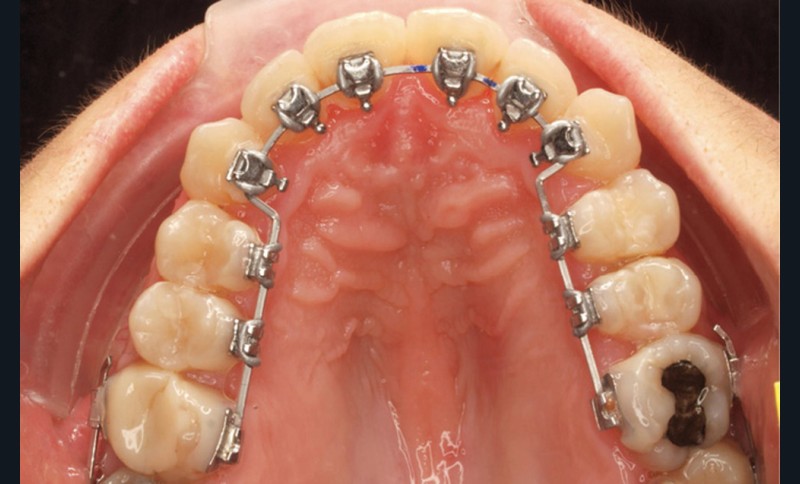

- Quatrième rendez-vous (fig. 2d) : des arcs TMA .017 x .017 sont posés. Les premières et deuxièmes molaires sont collées en vestibulaire avec un arc sectionnel NiTi 0,019×0,025.